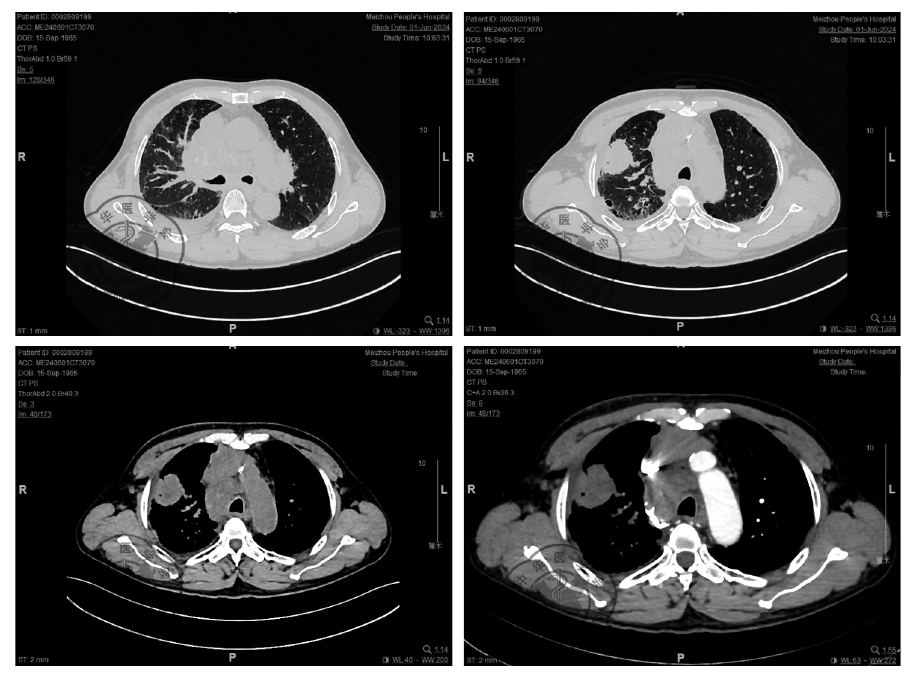

图1 患者胸部CT典型征象右肺上叶前段可见一团块影,截面约3.4 cm×4.5 cm,边界清,边缘可见分叶,其内密度欠均匀,增强扫描呈欠均匀轻度强化,右肺部分小叶间隔增厚,双肺透亮度增强,双肺支气管血管束增多、增粗、部分模糊,走行僵硬,双肺可见散在斑片状密度增高模糊影;双肺上叶可见散在大小不一薄壁囊状透亮影,边界清。心脏不大,心包内可见少量液性密度影,冠状动脉、主动脉壁可见斑点状钙化灶。右侧胸腔可见新月状液性低密度灶